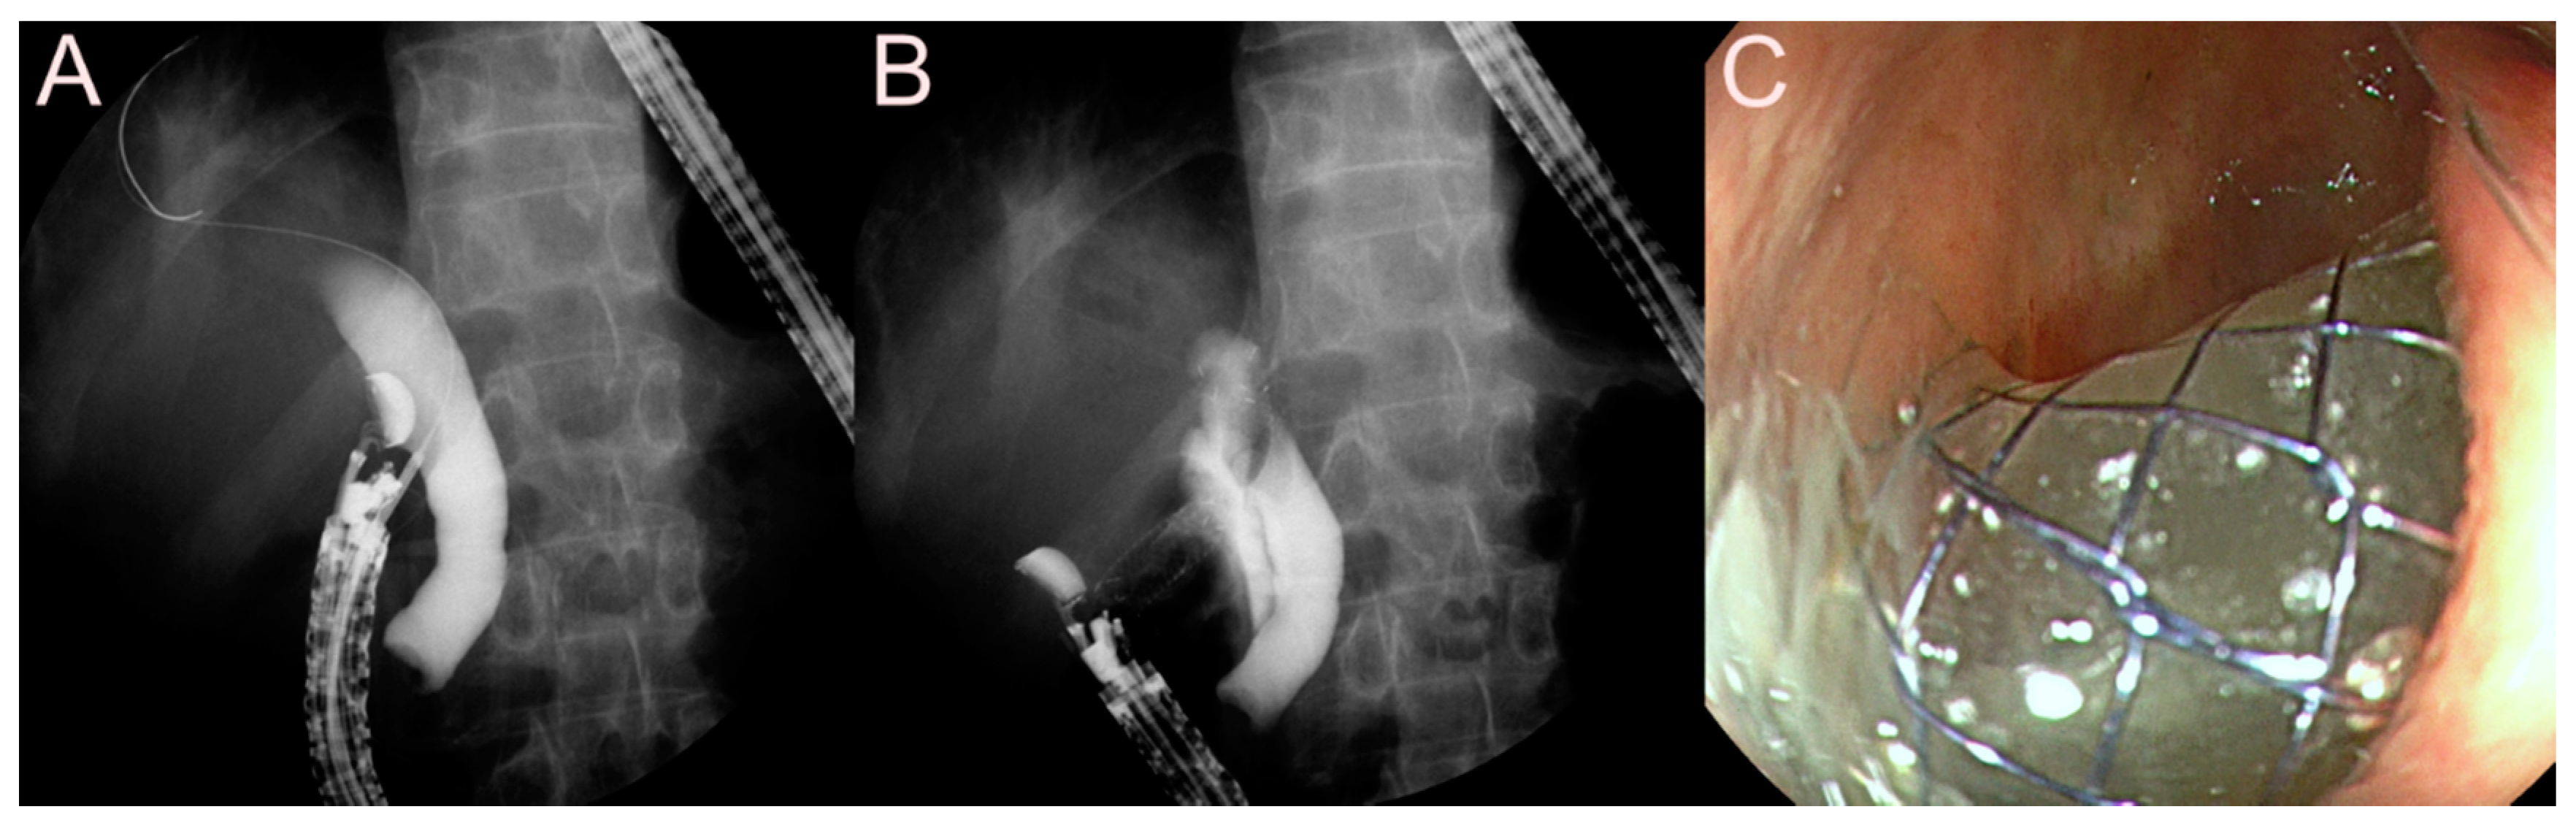

2.1.3. Use of the Lumen-Apposing Metal Stent (LAMS)